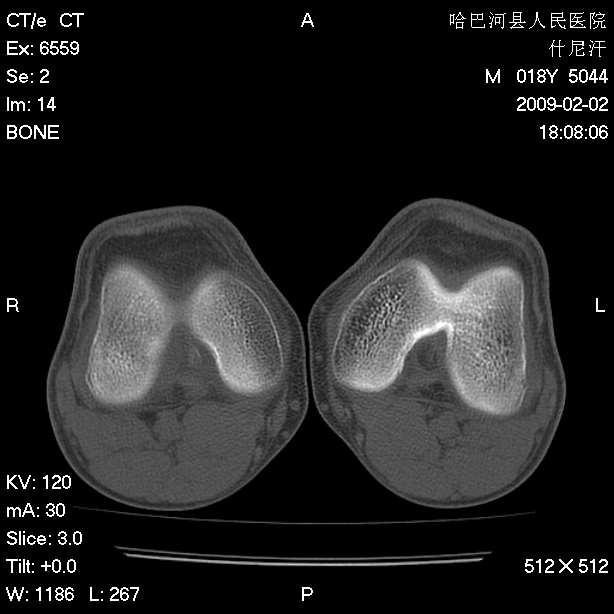

标题: CT17889:外伤后右膝关节反复疼痛3年余 [打印本页]

标题: CT17889:外伤后右膝关节反复疼痛3年余

ct未见明显异常。关节腔未见明显积液,半月板未见明显撕裂。但最好还是mri看看韧带及半月板情况。